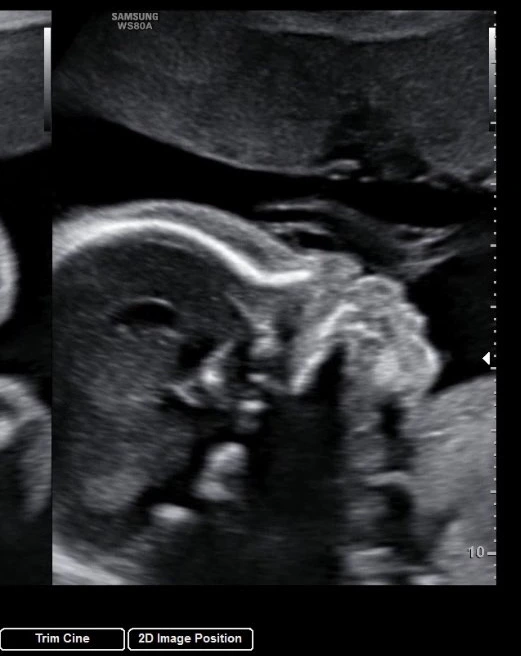

어엿한 어린이집 친구가 된 둘째 I 환영해 셋째야